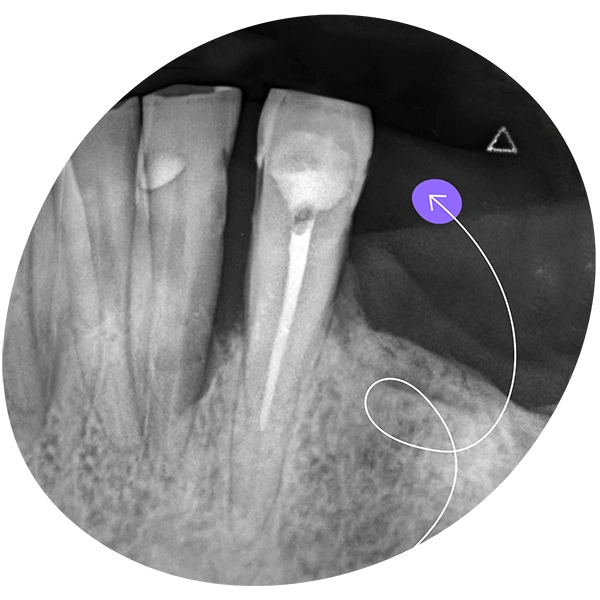

Es un tratamiento que remueve la parte interna dañada del diente para conservar la estructura exterior y mantener el diente en boca.

- Utilizando herramientas especiales se extrae la pulpa, limpiando minuciosamente toda la cavidad dental hasta el ápice de la raíz o las raíces (dependiendo del diente de que se trate, puede haber una, dos o cuatro raíces).

- La cavidad que quedó debe rellenarse con materiales especiales, procediendo a cerrar el agujero que se ha practicado para acceder a la pulpa, finalizando la restauración del diente.